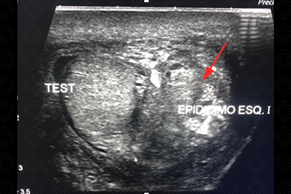

Descrição das figuras: Ultrassonografia da bolsa escrotal. Epidídimo esquerdo com volume muito aumentado e com hipervascularização ao Doppler colorido, compatível com epididimite aguda à esquerda.

• Ultrassonografia da bolsa escrotal: o epidídimo apresenta volume aumentado, sua ecogenicidade pode estar aumentada ou reduzida, mas em geral sempre heterogêneo e com fluxo aumentado no estudo com Doppler colorido. Edema de bolsa escrotal e uma hidrocele reacional comumente estão presentes. A inflamação pode atingir o testículo por contiguidade, levando a um quadro de orquiepididimite (figuras acima). Exame de escolha para população pediátrica ou adulta.